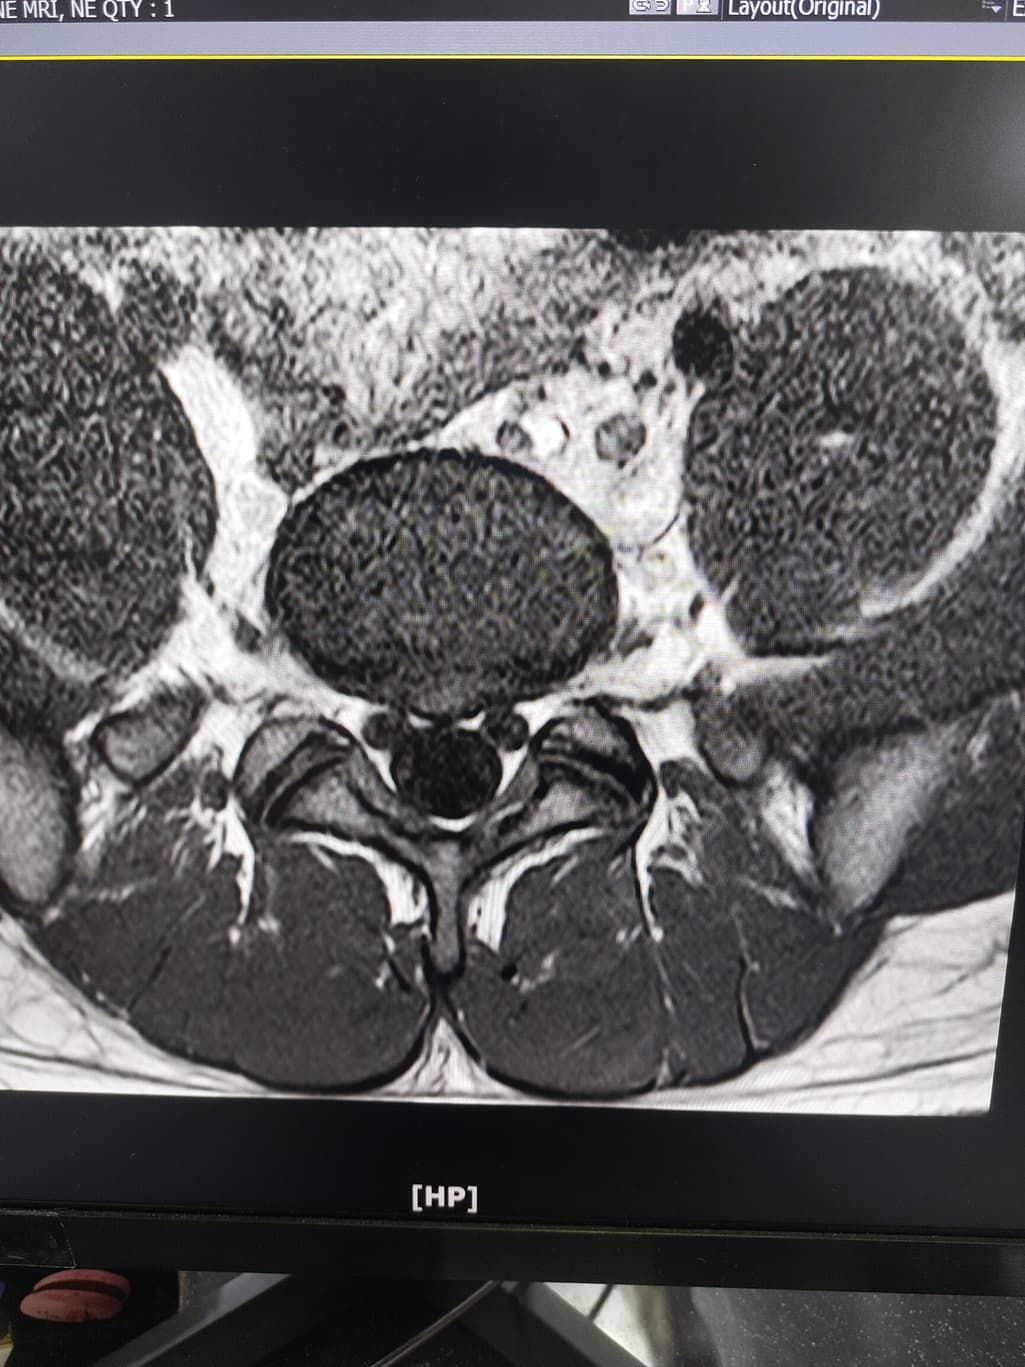

허리디스크 심한편인가요? [Mri 사진 첨부]

멸개월전부터 요추가 뻣뻣하고 시큰거리다가 최근에 좀 나아지긴 해도 만성적이라서 오늘 mri 찍고 허리디스크 진단받았습니다

(요추 맨 밑 천추 위 디스크)

신경이 심하게 눌리고 있지는 않은 것으로 보입니다. 충분히 휴식하여 주시고, 허리에 무리가 많이가는 자세는 당분간은 피해주시는 것이 좋습니다.